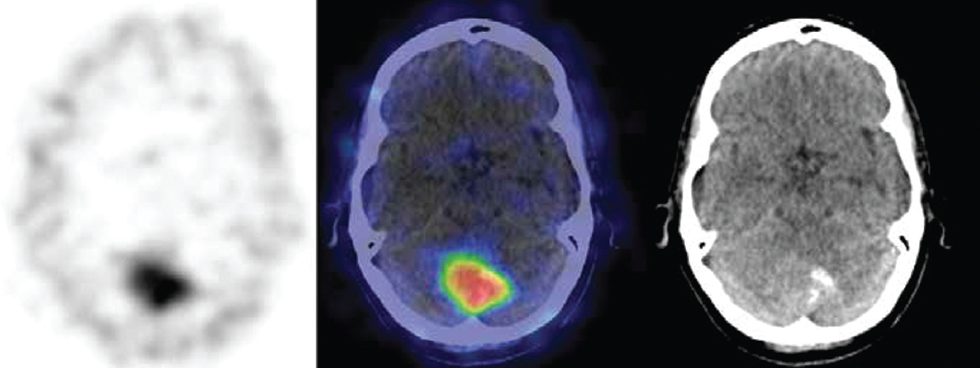

Рис. 4а. Очаг интенсивного накопления в проекции головки поджелудочной железы. Подозрение на НЭО для дальнейшего морфологического подтверждения / Fig. 4a. A focus of intense accumulation in the projection of the head of the pancreas. Suspicion of NET for further morphological confirmation

Рис. 4б. Очаговая гиперфиксация трейсера при ОФЭКТ/КТ в заднечерепной ямке. Окончательный диагноз: мененгиома затылочной доли / Fig. 4b. Focal hyperfixation of the tracer during SPECT/CT in the posterior fossa. Final diagnosis: meningioma of the occipital lobe

Представленные на рис. 4 сцинтиграммы показывают диагностическую эффективность РФЛП 99mTc-тектротид в качестве первичного прогностического тестирования НЭО. Кроме того, выявление опухолей мозга является важным и перспективным для дальнейших КИ с целью расширения показаний РФЛП, содержащих октреотид в качестве таргетного лиганда.